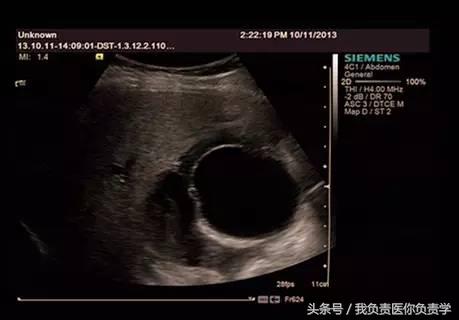

图1示胆囊体积明显增大,内部透声差

图2示胆囊周围可见液性暗区分布